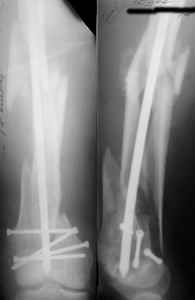

Отправитель: Enes M. Kanlic 13 Ноябрь 2004, 19:43

Dear colleagues,

1. Percutaneous nailing is truly minimally invasive technique, but, unfortunately, nails are not reliable in many hands.

Attached are few examples from our Hospital:

A. Difficult reductions, even in retrograde nailing (my preference, easier control of "small" distal fragment) and it is much, much harder to do it anterograde (Alex, do you have one good case in your collection of anterograde nailing in very distal fractures - as you have suggested that I

should have done it in my previously posted case?

Malpositioning is much too common (recurvatum, varus - valgus).

B. Fixation loosening: distal cutting of the nail, non-unions do happen (cases attached).

Locking Plating has more distal screws than any nail, fixed angles and provides much better fixation, especially in osteoporotic bone.